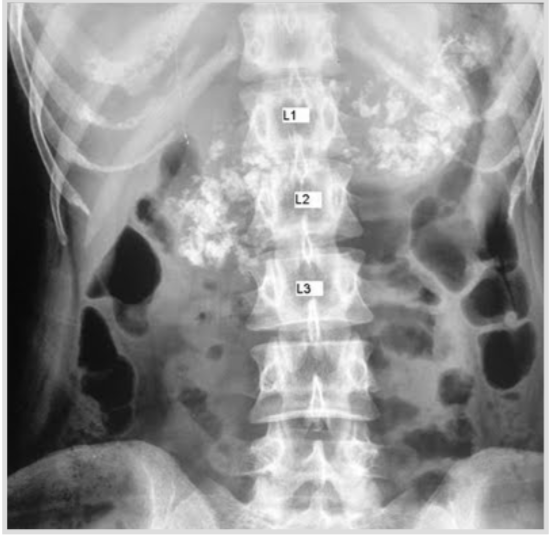

A 51 year old man complains of passing foul-smelling fatty stools. He noticed recent loss of weight as well; an abdominal x-ray was performed and findings can be observed as below. How would u manage this patient?

By supplementing him with pancreatic enzymes

Note: pancreatic calcifications are noted in the x-ray and are indicative of chronic pancreatitis